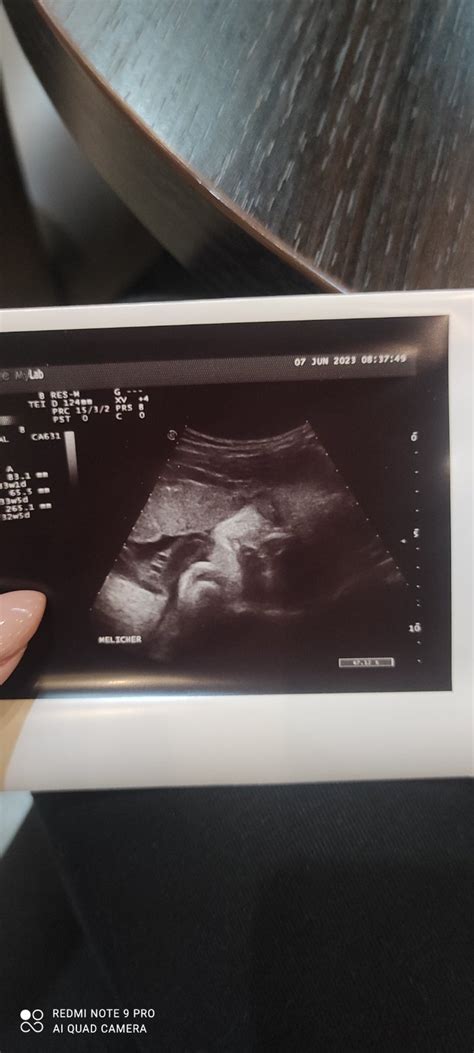

- Morfologický alebo Genetický Ultrazvuk: Toto vyšetrenie, často nazývané aj "veľký" ultrazvuk, je kľúčové pre detailné posúdenie vývoja plodu. Vykonáva sa zvyčajne medzi 20. až 22. týždňom tehotenstva. Lekár dôkladne prezrie všetky orgány a končatiny bábätka, aby vylúčil prípadné vývojové vady. Základná časť tohto ultrazvuku je hradená zdravotnou poisťovňou, zatiaľ čo rozšírený variant, tzv. genetický ultrazvuk, už spoplatnený byť môže. Je dôležité, aby toto vyšetrenie vykonal certifikovaný lekár s kvalitným prístrojovým vybavením.

Your pregnancy: 20 weeks